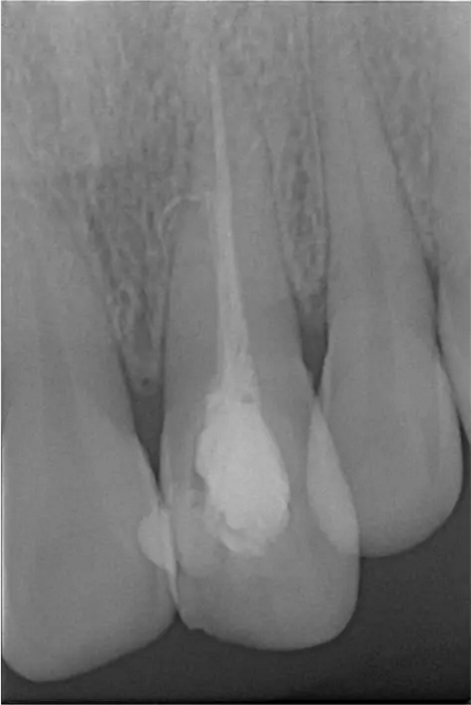

患者女,年齡35左右,牙位21,根管治療曾經(jīng)歷過外院四到五次等不同地方的處理,還是不能咬硬物,會有酸、軟、痛的情況出現(xiàn),偶有自發(fā)疼痛,2016年9月初,轉(zhuǎn)診至我處治療21。術(shù)前拍片發(fā)現(xiàn)根中部存在側(cè)穿,橡皮障下常規(guī)再治療,隨后減輕了軟和痛的情況。因為側(cè)穿,牙周膜受到牙膠尖等異物的持續(xù)刺激,酸軟的情況還是持續(xù)存在,所以決定行根尖外科手術(shù),采用MTA修補穿孔點。術(shù)后觀察半年左右,所有癥狀消除后,隨后熱牙膠充填。

術(shù)前診斷片